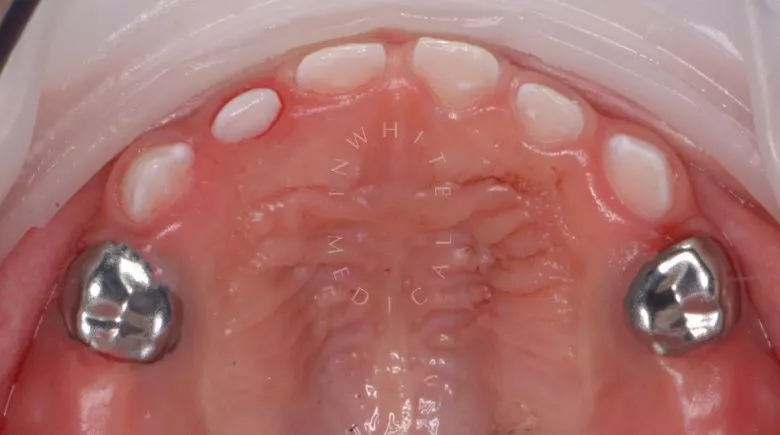

етская стоматология лечение под наркозом. Лечение под наркозом - установка коронок и профессиональная гигиена у детей - после процедуры